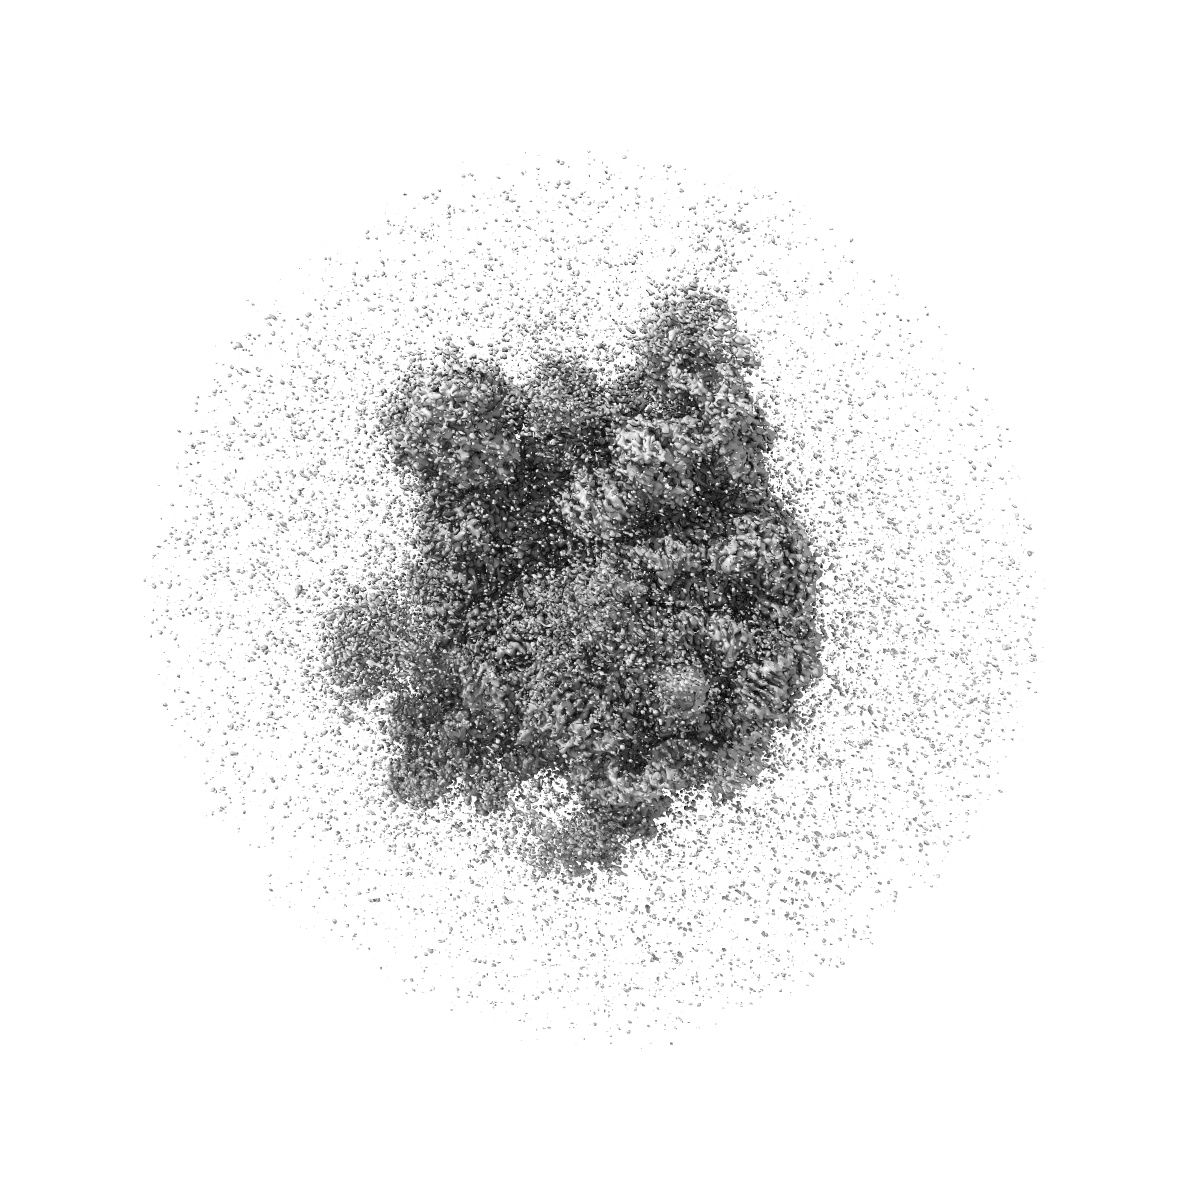

Structure of Mycobacterium smegmatis 50S ribosomal subunit bound to HflX and erythromycin:50S-HflX-B-Ery

Sample: Mycobacterium smegmatis 50S ribosome bound to HflX-GMPPNP complex and Erythromycin

HflX-mediated drug resistance through ribosome splitting and rRNA disordering in mycobacteria.

(2025) PNAS , 122 , e2419826122 - e2419826122